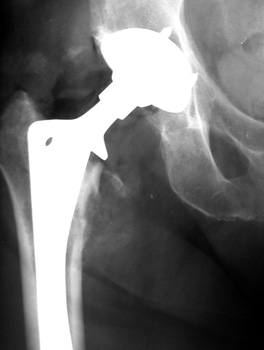

INFECTION—Markedly widened interfaces about acetabular and femoral components

INFECTION Progressive interface widening about acetabular component